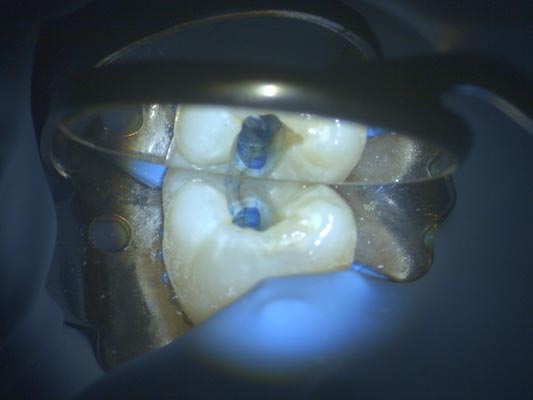

Imágenes Clínica de aumentos de Microscopio Leica M320:

Aumentos de microscopio de menor a mayor en un istmo de un molar superior: 6.4x, 10x, 16x, 25x, 40x

Localizamos el cuarto conducto en el mismo molar (segundo molar superior).

El tamaño final de la apertura con un tope de goma que mide 3mm de diámetro (apertura mínimamente invasiva).

Imágen: Imagen de fisura en un molar inferior visualizada con microscopio tras tinción con azul de metileno